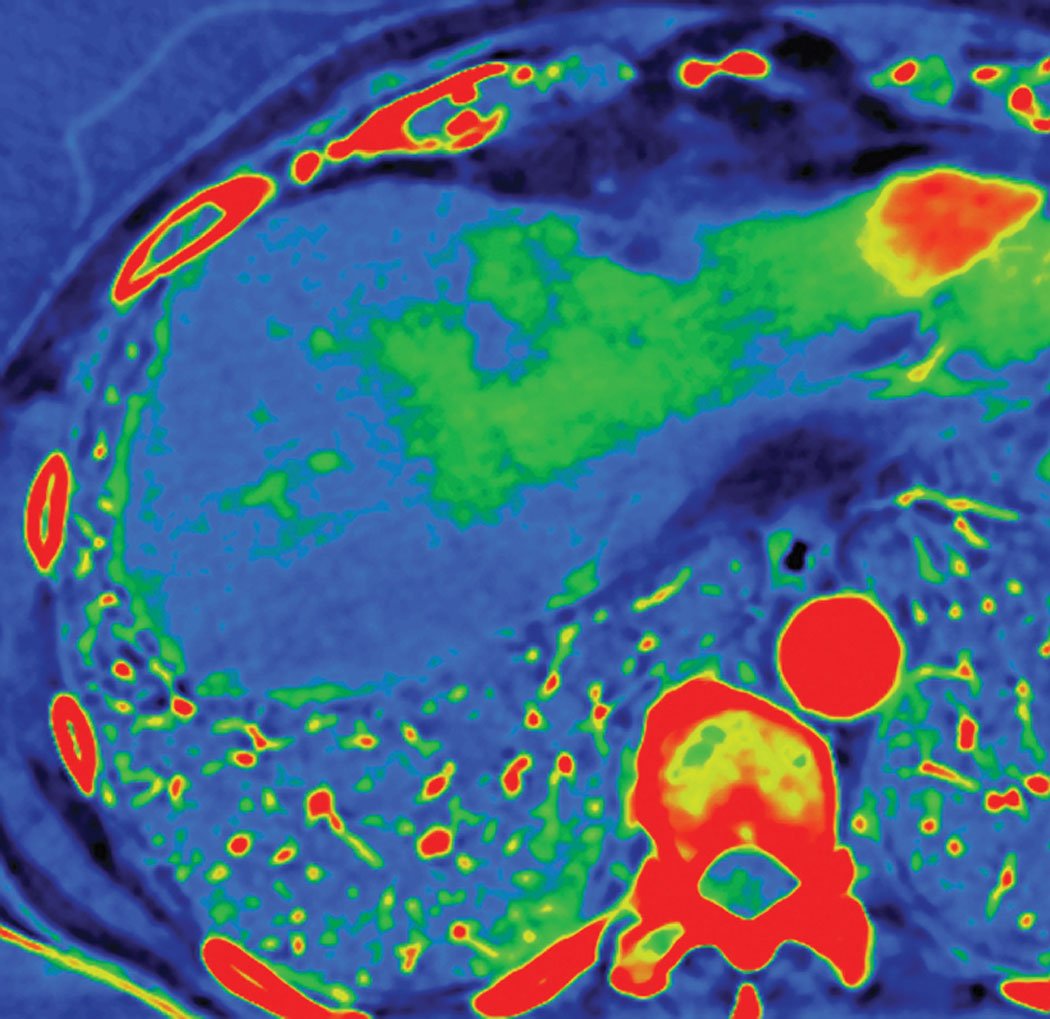

The solution has been provided through the advancement of spectral imaging, the next phase of CT’s evolution. By acquiring images at two different energy levels, the technique is able to differentiate the various elements in the body based on their material density or atomic numbers. The differences are displayed as varying shades of gray or even colors on the final image.

The system also is drawing strong interest from oncology, with the ability to create an “iodine map” overlay, as described by Vanderwall — essentially the viewer can see color-coded pixel-by-pixel density, allowing greater delineation of a tumor.

One of the most popular applications for GSI, and for spectral CT in general, is in abdominal scans, a fact confirmed by all three major vendors. Some of the earliest investigative uses for GSI focused on lesion characterization in abdominal scans, “an area where we commonly hear a lesion is too small to characterize,” stated Sahney. In a 2011 project, GE worked with an international coalition that included the Mayo Clinic and Massachusetts General Hospital in the United States. In the final published results, the scientific team found the dual-energy GSI was especially effective at identifying suspicious cysts in the kidneys, liver and pancreas.